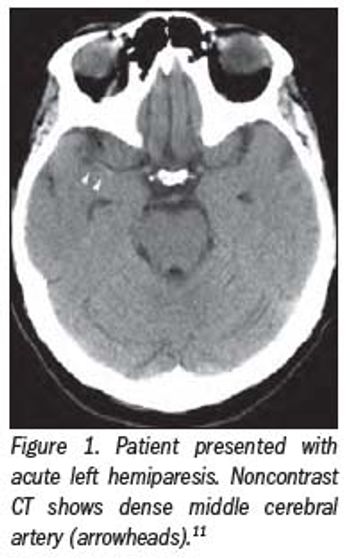

CT perfusion for stroke leaped from clinical discussion forums to the front pages in the last 13 months.